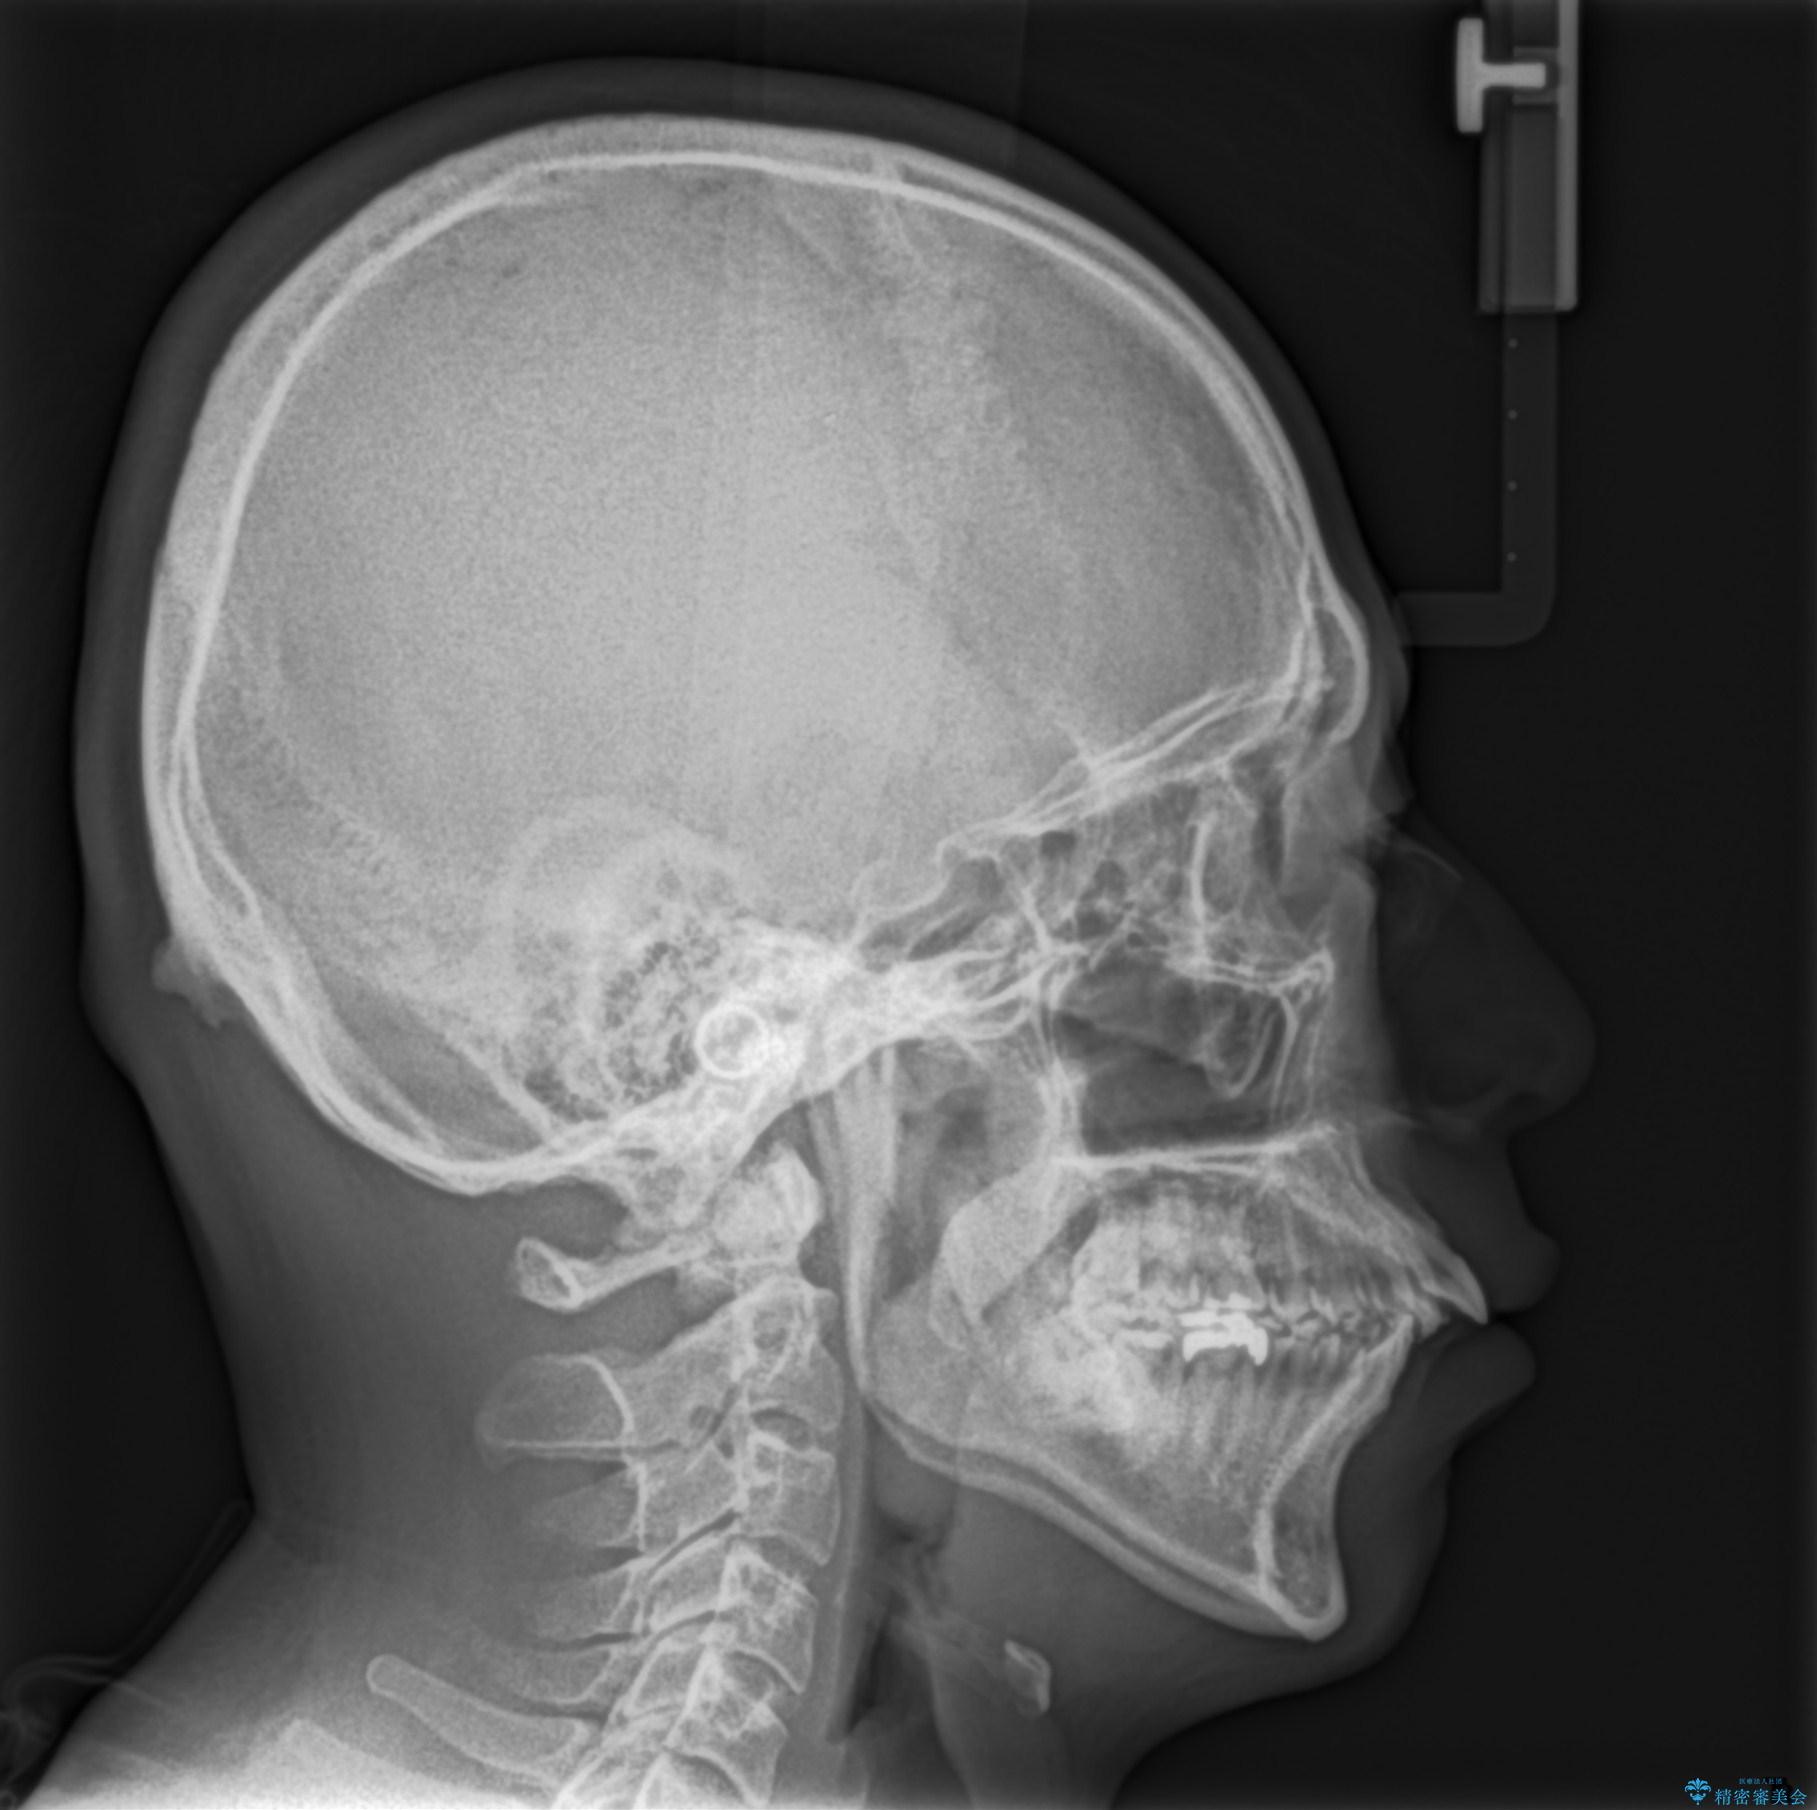

- 出っ歯が気になるとのことで来院されました。

上顎の前から4番目の歯を両側、合計2本抜歯して矯正する計画としました。

目立たない装置がご希望でしたので、上下裏側ワイヤー装置を選択されました。